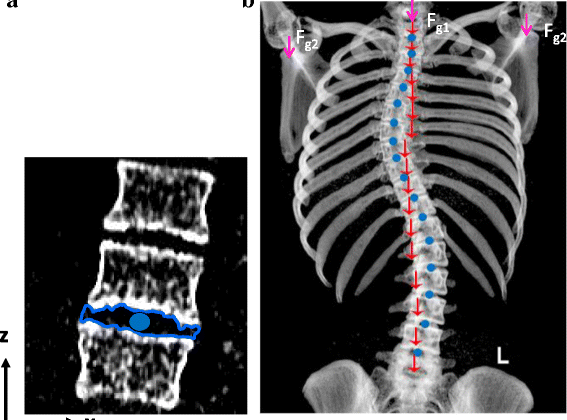

هدفت الدراسة إلى معرفة كيف تؤثر الجاذبية على العمود الفقري المصاب بالاعوجاج، وما إذا كانت تزيد من تطور الانحناء أو تغيّر شكل الفقرات بمرور الوقت. استخدم الباحثون تقنيات تصوير ثلاثية الأبعاد (3D CT) لمجموعة من المراهقين المصابين باعوجاج معتدل، وركّزوا على العزوم (moments) أو القوى الجانبية التي تؤثر على الفقرات بسبب الجاذبية.

أظهرت النتائج أن هناك نمطًا متكررًا من القوى الجانبية على فقرات الجزء الأوسط من الظهر (المنطقة الصدرية)، وخاصةً عند قمة الانحناء (apex).

بمعنى آخر، الجاذبية تُسبب قوة ضغط وانحناء مستمرة عند هذه النقطة، مما يجعلها أكثر عرضة للتفاقم.

كما لاحظ الباحثون أن بعض المرضى لديهم قوى إضافية في الجزء السفلي من الظهر (القطني) نتيجة للتعويض عن الانحناء العلوي.